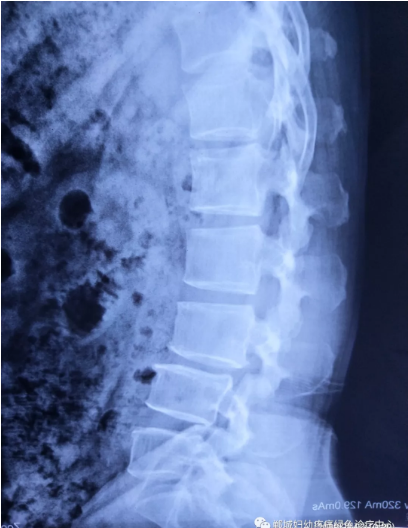

不經(jīng)意間聽到有人說醫(yī)院疼痛科可以不吃藥不打針,用無痛苦、無創(chuàng)傷的方法治療腰痛。陳女士就抱著試試看的心理來到了鄲城縣婦幼保健院疼痛科,疼痛科時(shí)慶祥主任詳細(xì)了解病情,結(jié)合腰椎磁共振及體征后告訴陳女士她不用手術(shù),通過腰椎脊柱定位周期減壓牽引系統(tǒng)(外星艙)也能解決腰痛、腰椎滑脫、腰椎反弓這些問題。陳女士未曾想到經(jīng)過十五天的治療后腰部及下肢放射性疼痛癥狀基本消失。陳女士感到十分激動(dòng)與感謝,就在當(dāng)?shù)匦l(wèi)生院做了一個(gè)腰椎正側(cè)位x片和之前的片子作對(duì)比,發(fā)現(xiàn)腰椎滑脫明顯改善。她說道:感謝鄲城縣婦幼保健院疼痛科的所有醫(yī)護(hù)人員、感謝外星艙脊柱減壓治好了我的腰痛,也感謝告訴我來這里的人,她的一句話,讓我省了好幾萬元的手術(shù)費(fèi)!

治療后